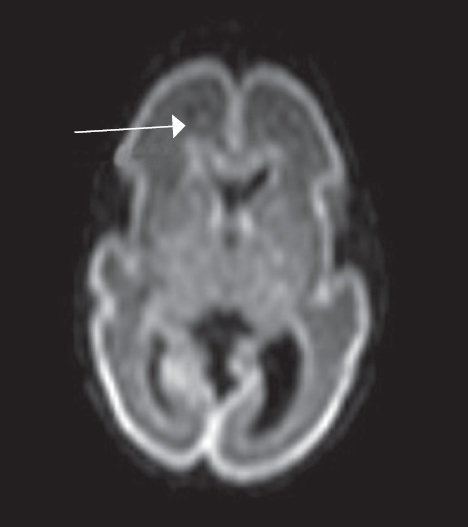

Как видно из таблицы, при выполнении МР-исследования в ПКВ 27–32 недели герминальный матрикс визуализировался у восьми недоношенных детей на ДВИ в виде усиления МР-сигнала вдоль боковых стенок боковых желудочков мозга, а также вдоль передних рогов над хвостатыми ядрами с обеих сторон (рис. 4). На Т2 ВИ герминальный матрикс достоверно выявлен у семи новорожденных (рис. 5). На Т1 ВИ герминальный матрикс достоверно выявлен у двух новорожденных (рис. 6). На последовательностях FLAIR герминальный матрикс не визуализировался.

Рис. 5. МРТ головного мозга недоношенного ребенка (ПКВ 28 недель). Т2 ВИ, аксиальная проекция, стрелками выделены участки герминального матрикса, расположенного вдоль наружных стенок боковых желудочков, гипоинтенсивный МР-сигнал

Fig. 5. MRI of preterm newborn (PCA 28 weeks), Т2-WI, axial plane. Arrows mark the areas of the germinal matrix located along the external walls of the lateral ventricles (hypointense MR signal)

В нашем исследовании герминальный матрикс визуализировался на Т1-импульсной последовательности только у небольшого числа детей (у двух детей) в возрастной группе до 32 недель ПКВ в виде гиперинтенсивного сигнала от нижней стенки переднего отдела боковых желудочков. На Т2 ВИ герминальный матрикс выявляется у большего числа детей (у 7 из 9 детей) в возрастной группе 27–32 недели ПКВ, изменение интенсивности сигнала от герминального матрикса представлено гипоинтенсивным МР-сигналом от передних отделов и наружных стенок тел боковых желудочков. Использовать Т2-импульсную последовательность в оценке церебральной зрелости у недоношенных детей рекомендует S. Counsell [4]. Он отмечает снижение интенсивности Т2-сигнала от латеральных стенок и передних отделов боковых желудочков у недоношенных детей в ПКВ до 32 недель. Как полагает S.J. Counsell, сохранение гипоинтенсивного Т2-сигнала от этих структур у недоношенных детей старше 32 недель ПКВ может свидетельствовать о нарушении глиальной миграции [5].